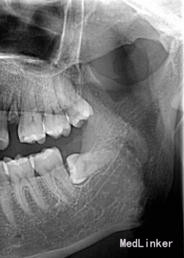

左下8水平阻生拔除

查体 辅查

行曲面断层片

患者,男,25岁,要求拔除左下颌水平阻生牙齿,平素体质一般,无药物、食物过敏史,无高血压、心脏病等系统病史